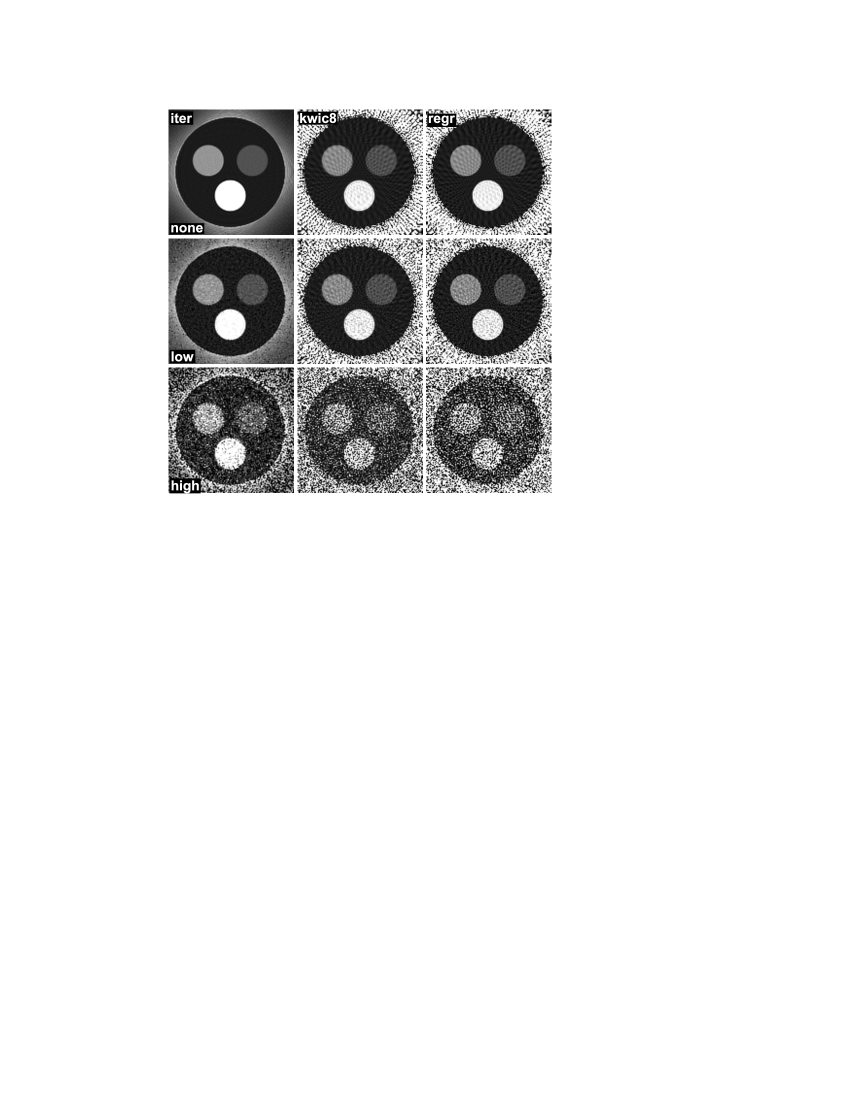

4.2 Simulated Data

Figure 5 shows relaxivity maps from simulated data estimated with the proposed method, the KWIC method, and direct gridding (the proton density maps are not shown as the proton density was set to a constant value within the phantom). As in the prior figures, an identical windowing function has been used for all relaxivity maps within the figure, so that absolute relaxivity values were equally mapped to grayscale values. The upper row corresponds to a fully sampled data set (4032 spokes, 252 repetitions), and, hence, the number of spokes for each echo time complies with the Nyquist theorem in the sense that the angular distance between neighboring spokes is less or equal to . In this case, all three approaches yield maps without any streaking artifacts. However, the maps created by KWIC and gridding present with somewhat stronger Gibbs ringing artifacts, which are especially visible within the smaller compartments. The middle row corresponds to the degree of undersampling that was used in the experiments presented in Fig. 1 – Fig. 3 (512 spokes, 32 repetitions). Here, streaking artifacts appear for KWIC and gridding, whereas the iterative reconstruction is free from these artifacts. The bottom row shows maps for a high degree of undersampling, corresponding to the highest undersampling factor presented in Fig. 4 (128 spokes, 8 repetitions). For such an undersampling, minor streaking artifacts arise also in the iterative reconstruction, while the KWIC and gridding reconstructions exhibit severe streaking artifacts. Noteworthy, only a single receive channel was generated in the simulations, and, thus, it clarifies that the proposed method offers an improvement also without exploiting localized coil sensitivities, which is implicitly done for experimental multi-coil data due to the better conditioning of the problem. Table 2 summarizes a region-of-interest (ROI) analysis of the relaxivity maps from Fig. 5, where identical regions were analyzed in all maps. In all cases, the iterative approach estimates the signal relaxivity with higher accuracy than gridding or KWIC. Interestingly, even in the fully-sampled case, significant deviations occur for the KWIC and gridding reconstruction. These deviations result from the strong ringing effects that are apperent in Fig. 5, which appear to be more pronounced for radial acquisitions than for Cartesian acquisitions. Hence, the strong signal from the surrounding compartment smears into the quickly decaying compartments, which causes a bias of the signal intensity in the time-resolved images. The iterative approach seems to better cope with this situation.

Finally, Fig. 6 shows relaxivity maps estimated from simulated data with different degrees of added Gaussian noise (512 spokes, 32 repetitions). It demonstrates that the proposed approach works stable also under noisy conditions, which is somewhat obvious as the matching of the maps to the measured data is done in a least-squares way. The maps estimated with KWIC and gridding present with a slightly higher noise level. The results of a ROI analysis of the maps are summarized in Table 1.